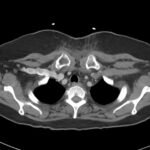

Retropharyngeal abscess (RPA) is an uncommon yet potentially life-threatening condition that is more often seen in young children and may be misdiagnosed in adults presenting with atypical features.1 Retropharyngeal abscess results from spread of antecedent upper respiratory tract infection or traumatic inoculation via foreign body ingestion or medical instrumentation. Clinically, RPA may present with fever, pharyngitis, neck pain, and dysphagia. Diagnosis is often confirmed with imaging studies. We present a case of a 66-year-old female with asthma, hypertension, and gastroesophageal reflux disease (GERD) who presented to the emergency department (ED) for evaluation of neck fullness, shoulder pain, dysphagia, and abdominal pain starting less than 24 hours prior to presentation. Computed tomography (CT) revealed a prevertebral/retropharyngeal fluid collection from the odontoid tip to the C4 vertebral body measuring 5.4 x 1.0 x 3.3 centimeters (cm) in size with associated edema at the left neck base extending into the upper chest, suggestive of retropharyngeal abscess. The patient received intravenous (IV) vancomycin and piperacillin/tazobactam and was transferred to a higher level of care for otolaryngologist evaluation. The patient remained stable without airway compromise while in our department. This case underscores challenges in diagnosing atypical presentations of RPA in adults, emphasizing timely recognition to prevent complications.